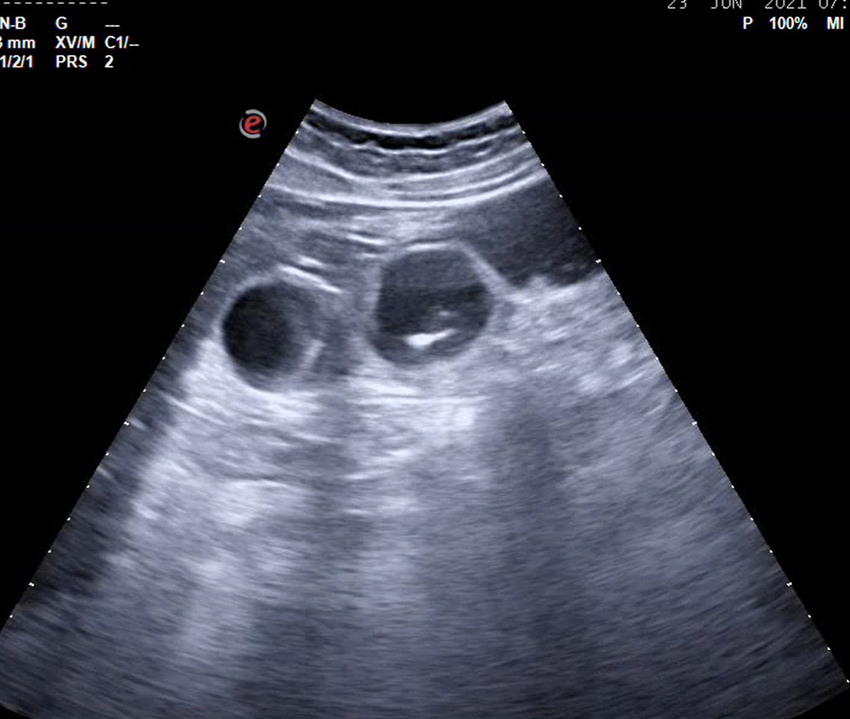

Mujer de 35 años con dolor en hemiabdomen inferior y fiebre: apendicitis aguda perforada.